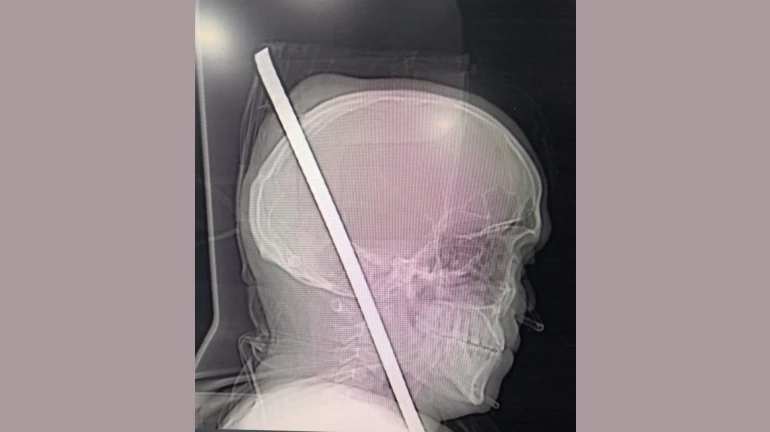

यूँ ही डॉक्टरों को भगवान नहीं कहा जाता, मजदूरी कर अपने परिवार का पेट पालने वाले राकेश जाधव के साथ जो हुआ उसे केवल भगवान का ही सहारा था। दरअसल राकेश एक निर्माणाधीन बिल्डिंग में काम करते 13 फूट की ऊंचाई से नीचे गिर पड़ा,और उसके सीने में एक लोहे का रॉड घुस गया जो सिर से होते हुए बाहर निकल आया था। आख़िरकार डॉक्टरों ने राकेश को बचा लिया, लेकिन कैसे पढ़िए इस रिपोर्ट में।

मंगलवार 20 नवंबर के दिन चेंबूर की एक निर्माणाधीन बिल्डिंग में राकेश जाधव काम कर रहा था। काम करते समय राकेश का संतुलन अचानक बिगड़ गया और वह 13 फूट नीचे आ गिरा। इस हादसे में राकेश के सीने में एक 3 फूट लोहे का रॉड घुस गया जिसका एक सिरा सिर के रास्ते बाहर निकल आया। राकेश का काफी खून बह चुका था, उसे तत्काल जेन अस्पताल में दाखिल कराया गया।